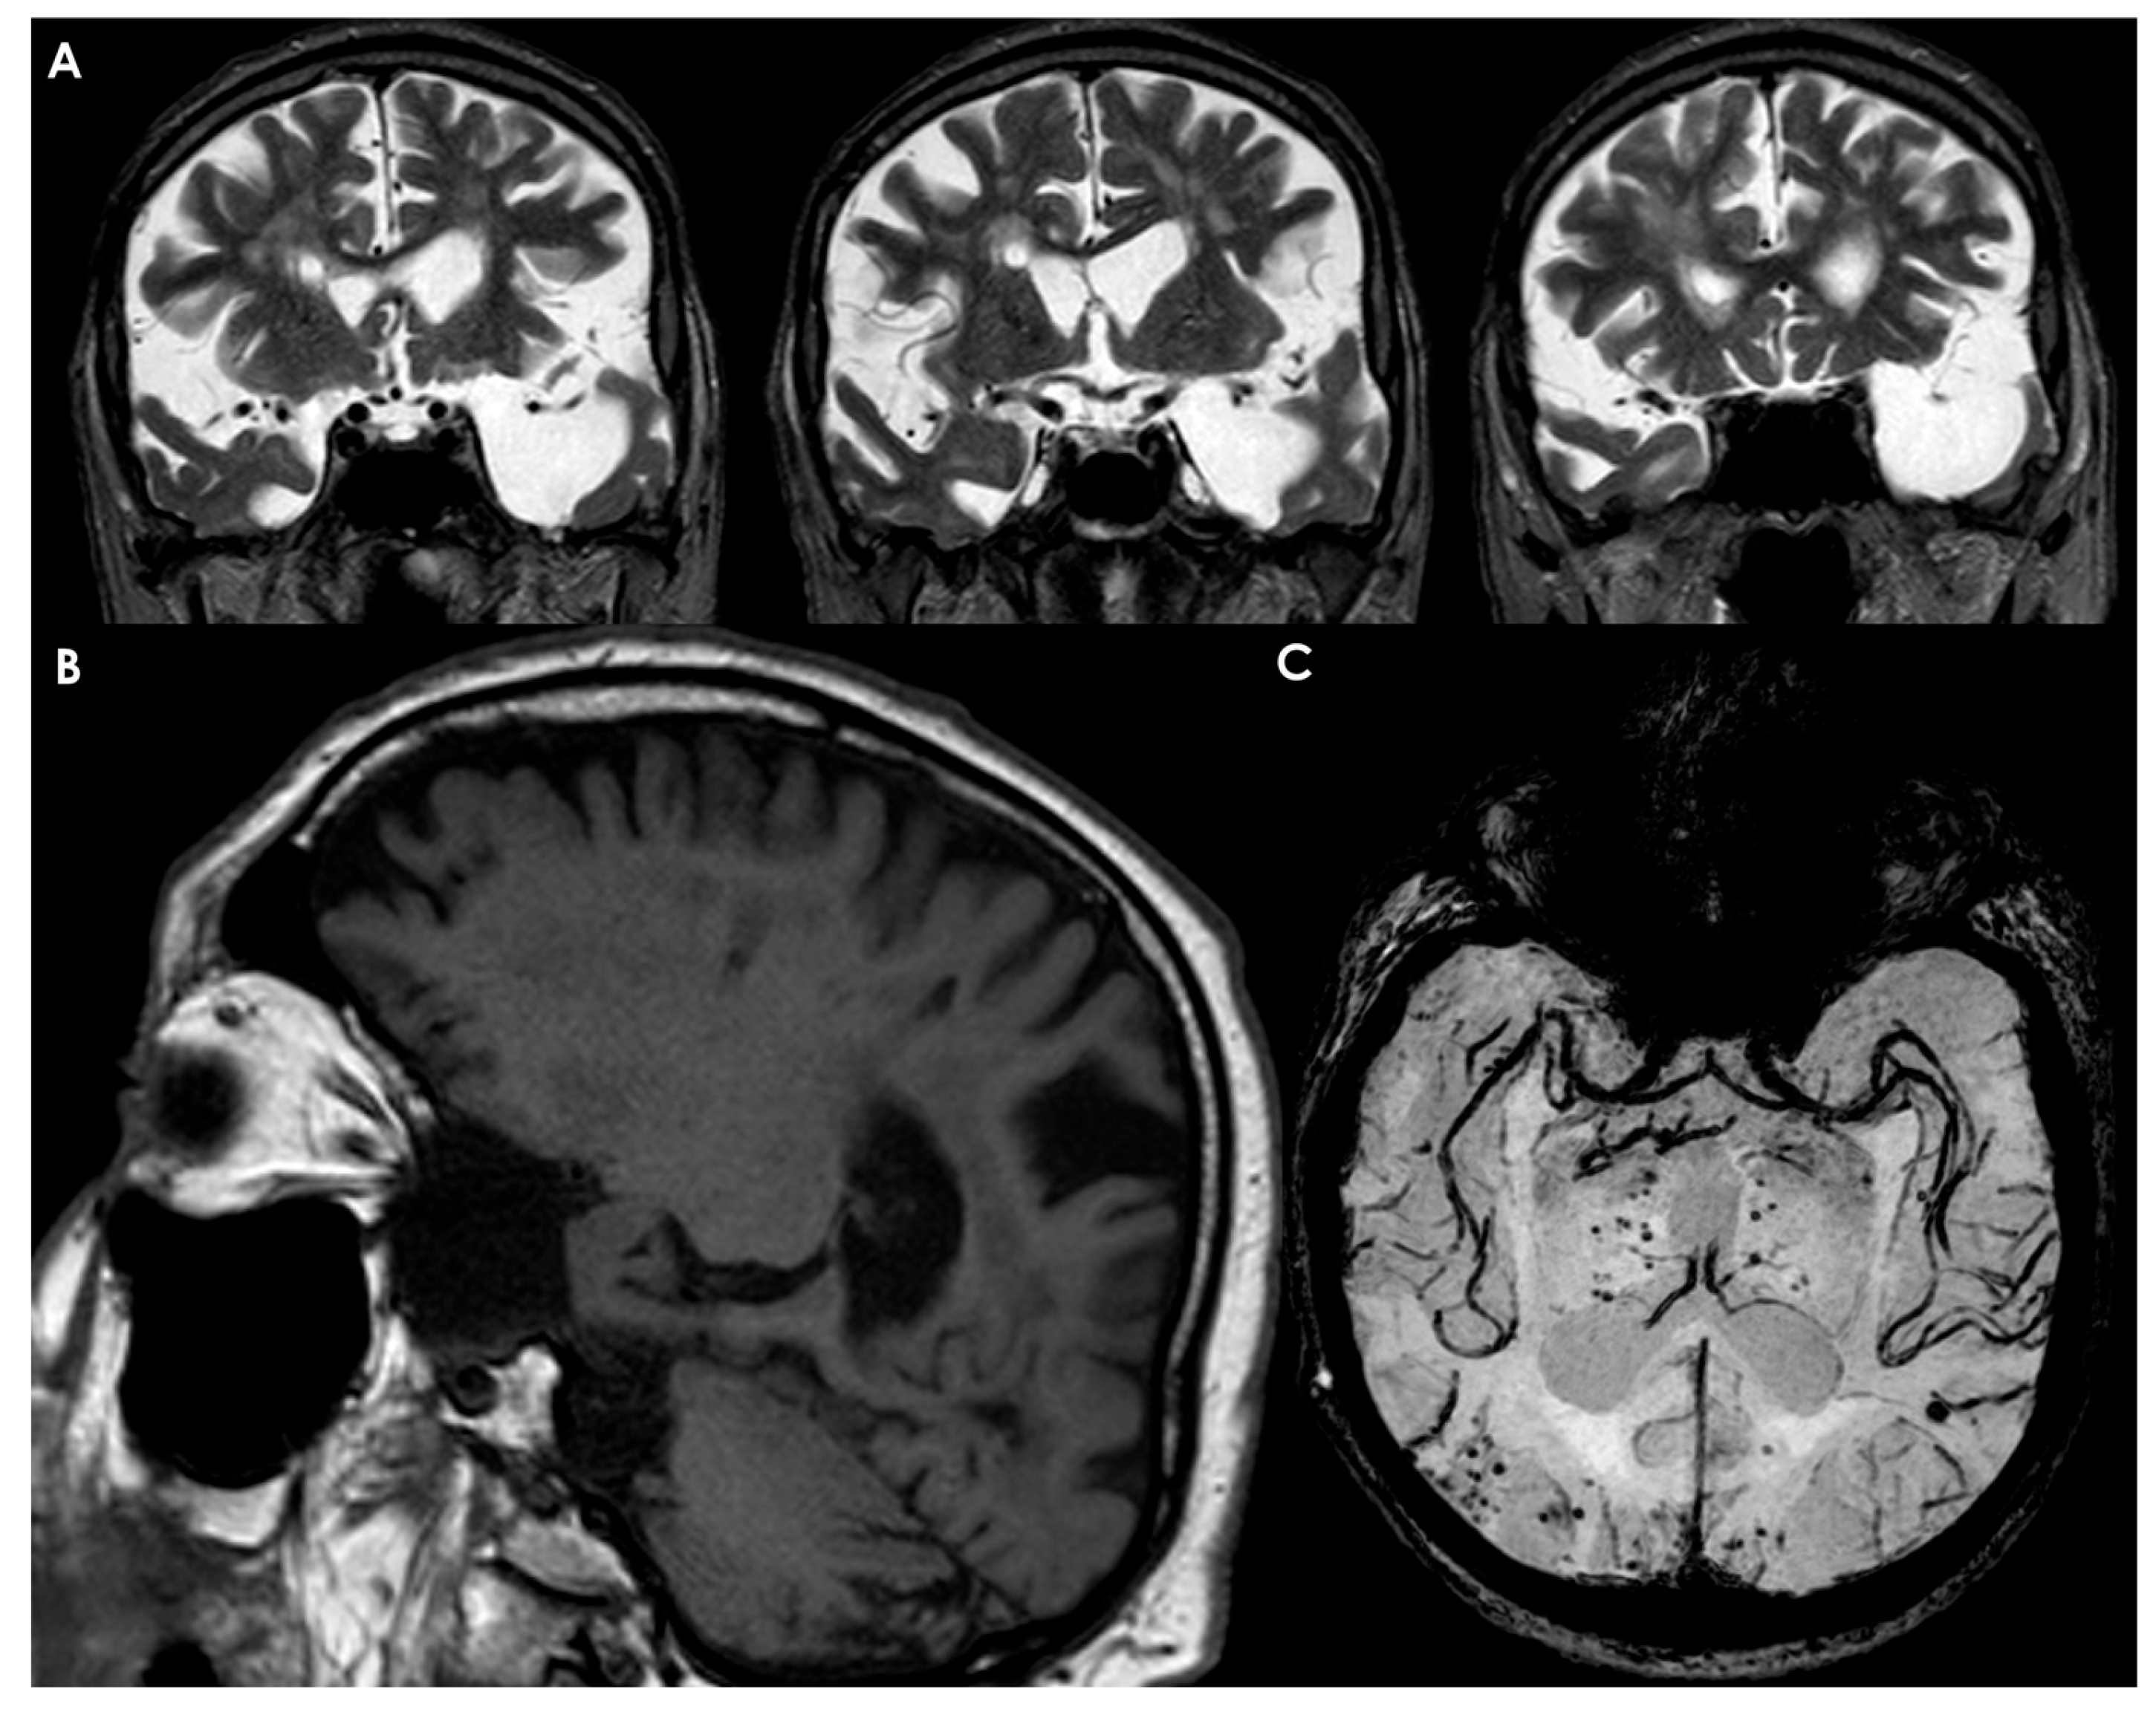

4.3. Arachnoid Cysts

- Sylvian fissure: 103 (49%);

- Cerebellopontine angle: 22 (11%);

- Supracollicular area: 21 (10%);

- Vermian area: 19 (9%);

- Sellar and suprasellar regions: 18 (9%);

- Interhemispheric fissure: 10 (5%);

- Cerebral convexity: 9 (4%);

- Clival region: 6 (3%).

- Small, spindle-shaped lesion confined to the anterior temporal fossa.

- Compresses the anterior temporal pole posteriorly.

- Does not affect the ventricles or midline structures.

- Demonstrates free communication with the subarachnoid space and basal cisterns.

- Generally associated with mild symptoms due to limited compression on surrounding brain structures.

- Medium-sized lesion, roughly triangular or quadrangular in shape.

- Occupies the anterior and middle parts of the temporal fossa, leading to a shortened temporal lobe.

- Extends into the Sylvian fissure, resulting in a widely opened fissure with the insula exposed.

- Communication with the subarachnoid space and cisterns is present but appears less pronounced than in Type I.

- Clinical Implications: Can lead to moderate symptoms due to increased compression on the temporal lobe and adjacent structures.

- Large, round or oval-shaped lesion occupying nearly the entire temporal fossa and a significant area of the cerebral hemisphere.

- Results in atrophy of the temporal lobe and severe compression of the frontal and parietal lobes.

- Involvement of the ventricles and midline structures is observed.

- Unlike the first two types, Type III does not exhibit communication with the subarachnoid space and cisterns.

- Clinical Implications: Often associated with severe neurological deficits due to extensive compression and structural changes in the brain.